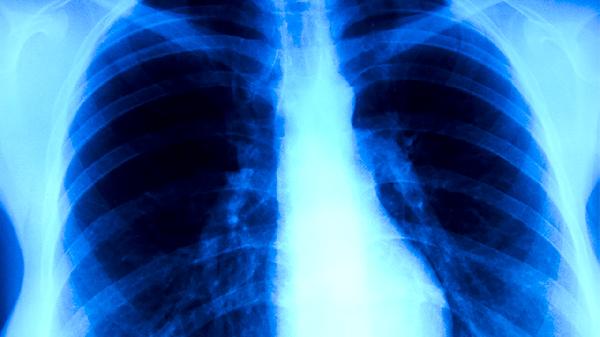

肺结核可能由结核分枝杆菌感染、免疫力低下、长期接触传染源、营养不良、慢性疾病等因素引起。肺结核是由结核分枝杆菌感染引起的慢性传染病,主要表现为咳嗽、咳痰、低热、盗汗等症状。

结核分枝杆菌是肺结核的主要致病菌,通过呼吸道飞沫传播。当感染者咳嗽、打喷嚏或说话时,含有结核分枝杆菌的飞沫会悬浮在空气中,被他人吸入后可能导致感染。结核分枝杆菌进入肺部后,可在肺泡中繁殖,引发炎症反应。治疗肺结核通常需要联合使用抗结核药物,如异烟肼片、利福平胶囊、吡嗪酰胺片等。